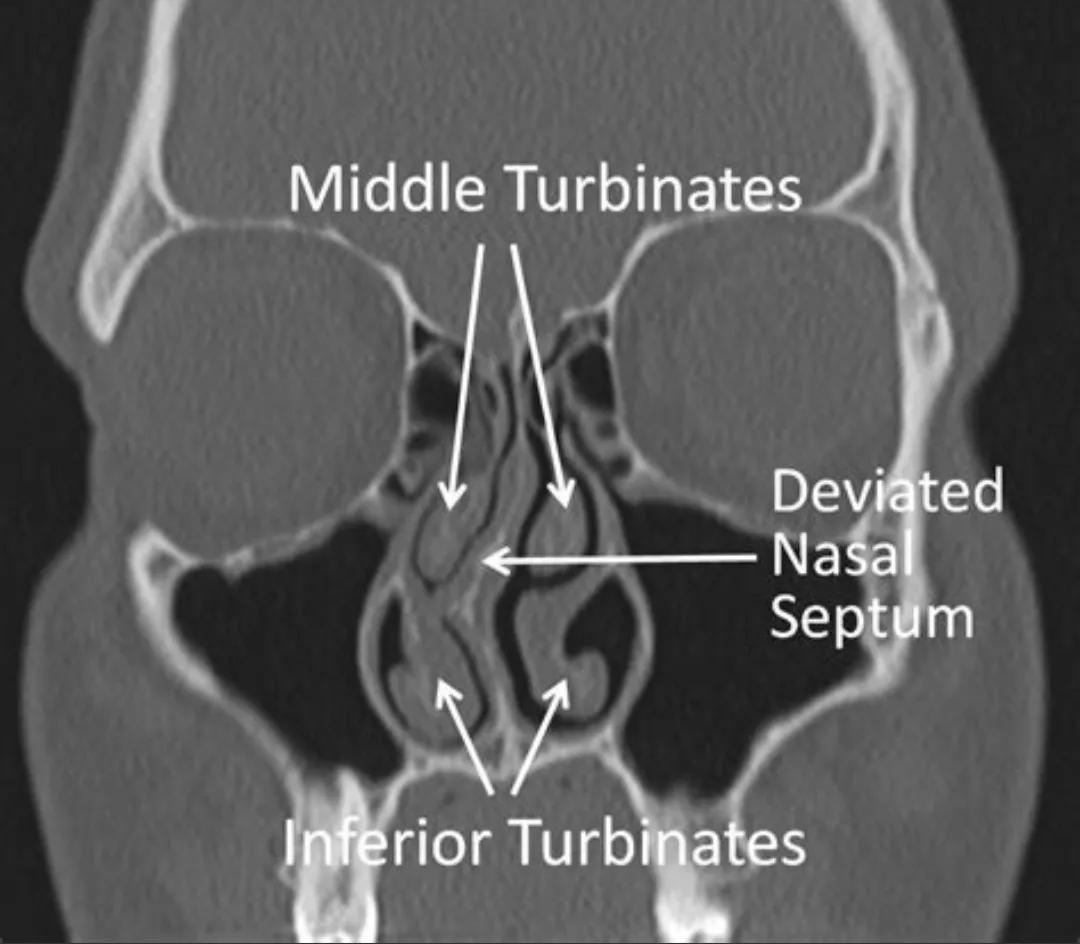

前者主要是气味分子传导到嗅区的通道被堵了,味道上不去就闻不到,主要见于鼻腔炎症性(鼻炎、鼻息肉)、结构性(鼻中隔偏曲)、肿瘤性因素梗阻了气流通道,就像鼻子捏住了就闻不到味道一个道理,这种情况一般只要解除(药物或者手术治疗)了梗阻因素,嗅觉就有希望得到恢复,但是针对长时间梗阻的人来说往往嗅神经长时间得不到气味的刺激可能会出现废用性萎缩(类似于肌肉长期不收缩就会逐渐萎缩变小),即使梗阻解除也未必能恢复,因此发现嗅觉减退要及时就诊,争取能得到嗅觉的恢复。

图解:鼻中隔偏曲导致嗅区空间变小